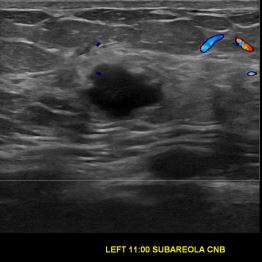

상기환자는 외부검사이상소견으로 내원하신 40대중반 여성분으로 의심스러운 좌측혹 조직검사 시행해 침윤성암으로 진단되었습니다